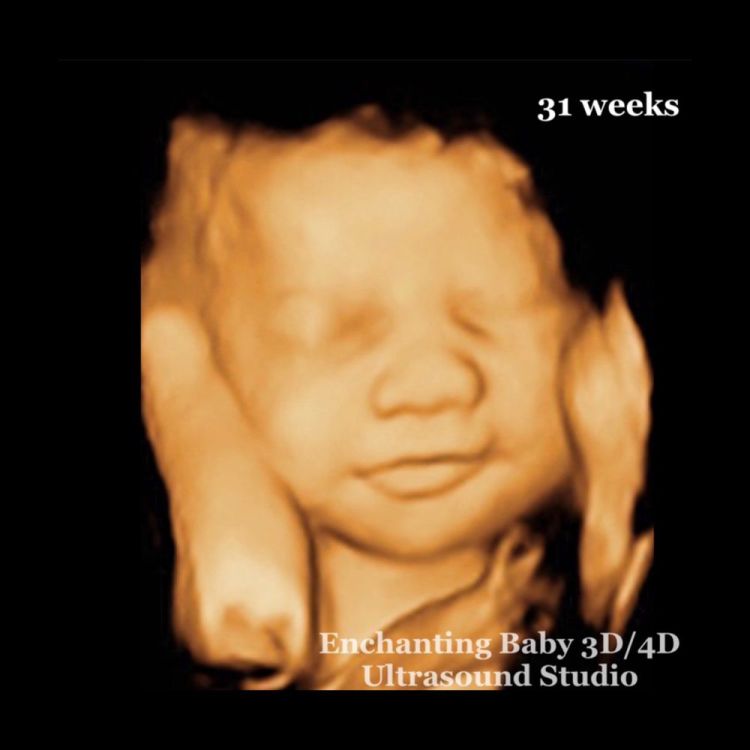

Ultrasonido 3D vs 4D: ¿Cuál es la diferencia?

Entonces, ¿qué es una ecografía 4D? Mientras que los ultrasonidos 3D producen imágenes claras de su bebé, los ultrasonidos 4D van un paso más allá al capturar videos. Obtendrá una imagen de su bebé con movimiento de acción en vivo, para que pueda ver lo que está haciendo en ese mismo segundo: sonriendo, sonriendo, chupándose el dedo, menos el breve retraso de los ultrasonidos tradicionales.

Las mujeres embarazadas pueden obtener una ecografía 3D en cualquier momento, ya sea además o en lugar de una ecografía bidimensional tradicional. Los profesionales médicos pueden preferir realizarlos entre aproximadamente 24 y 34 semanas. Durante este tiempo, el bebé se desarrollará lo suficiente como para verlo correctamente. También hay menos riesgo de que el líquido o la posición en la pelvis bloqueen los resultados.